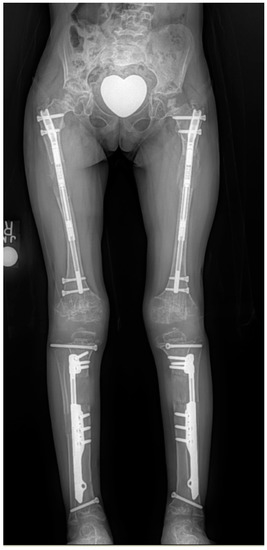

Extensive Limb Lengthening for Achondroplasia and Hypochondroplasia

by Dror Paley

Children 2021, 8(7), 540; https://doi.org/10.3390/children8070540 - 24 Jun 2021

Extensive limb lengthening (ELL) was completed in 75 patients: 66 achondroplasia and 9 hypochondroplasia. The average lengthening was 27 cm for achondroplasia (12–40 cm) and 17 cm for hypochondroplasia (range 10–25 cm). There were 48 females and 27 males. Lengthening was done either [...] Read more.

Extensive limb lengthening (ELL) was completed in 75 patients: 66 achondroplasia and 9 hypochondroplasia. The average lengthening was 27 cm for achondroplasia (12–40 cm) and 17 cm for hypochondroplasia (range 10–25 cm). There were 48 females and 27 males. Lengthening was done either by 2-segment (14 patients; both tibias and/or both femurs) or by 4-segment lengthenings (64 patients; both femurs and tibias at the same time). Most patients also had bilateral humeral lengthening. Patients had 2 or 3 lower limb lengthenings and one humeral lengthening. Lengthenings were either juvenile-onset (31), adolescent-onset (38) or adult-onset (6). The average age at final follow-up was 26 years old (range 17–43 years). There were few permanent sequelae of complications. The most serious was one paraparesis. All patients returned to activities of normal living and only one was made worse by the surgery (paraparesis). This is the first study to show that ELL can lead to an increase of height into the normal height range. Previous studies showed mean increases of height of up to 20 cm, while this study consistently showed an average increase of 30 cm (range 15–40 cm) for juvenile-onset and mean increase of 26 cm (range 15–30 cm) for adolescent-onset. This results in low normal height at skeletal maturity for males and females. The adult-onset had a mean increase of 16.8 (range 12–22 cm). This long-term follow-up study shows that ELL can be done safely even with large lengthenings and that 4-segment lengthening may offer advantages over 2-segment lengthening. While all but the more recent cases were performed using external fixation, implantable limb lengthening promises to be an excellent alternative and perhaps an improvement. Full article